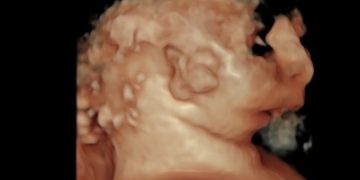

Cari soci, finalmente online le soluzioni dei casi del mese di Luglio Grazie a Carlotta Zorzi e Daniele Di Mascio!! Caso 1 - video [pdf-embedder url="https://www.sieog.it/wp-content/uploads/2024/07/risposta-Casodelmese_Luglio20241.pdf" title="risposta...